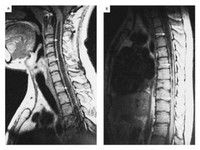

1.CT、MRI能夠清晰觀察脊髓的內部結構變化以及其他組織對脊髓的壓迫情況。2.MRI診斷脊髓出血為敏感和準確。觀察病灶更為敏感。

MRI可早期顯示脊髓水腫的部位、程度及範圍與萎縮變細等晚期表現.急性期增強後可顯示病灶部位輕度強化.